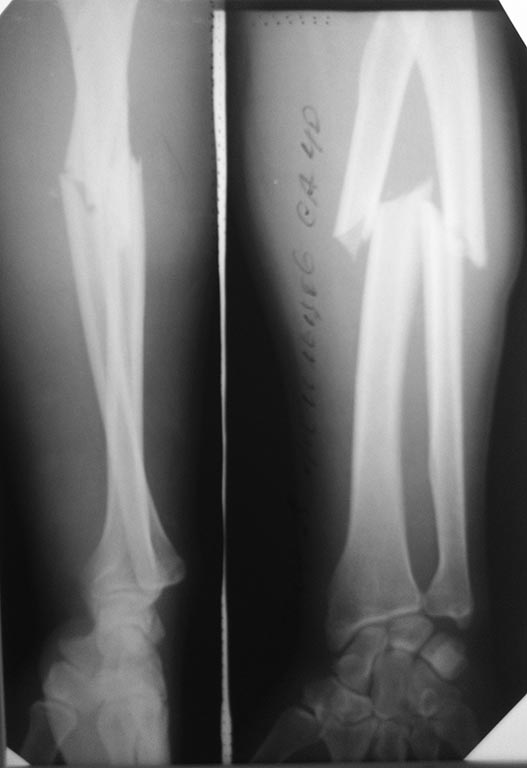

21.04.15 явился на консультативный прием с жалобами на боль в области

перелома при выполнении ЛФК. Выполнена контрольная Р-графия (снимок 3),

признаки консолидации сомнительны.

Прошу помощи уважаемого сообщества по дальнейшей тактике лечения.